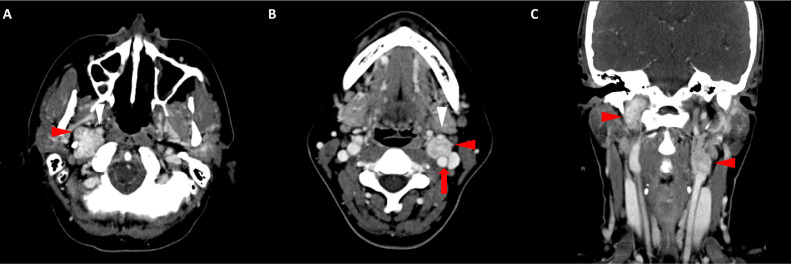

胸部、腹部和骨盆的對(duì)比增強(qiáng)動(dòng)脈和靜脈期 CT 顯示多個(gè)圓形、主要是血管豐富的異質(zhì)腫塊,具有囊性和實(shí)性成分,起源于胃底和胃體(圖 2-4)。 病變部分呈外生結(jié)構(gòu),被認(rèn)為位于粘膜下層。 在頸部多發(fā)同步性副神經(jīng)節(jié)瘤的情況下,賊初的鑒別診斷包括多發(fā)性副神經(jīng)節(jié)瘤、多發(fā)性 GIST 以及轉(zhuǎn)移性疾病。

Fig. 3

圖 3:多個(gè)胃腸道間質(zhì)瘤的冠狀和矢狀圖像。 (A 和 B)冠狀動(dòng)脈相對(duì)比增強(qiáng) CT 圖像顯示胃賁門產(chǎn)生的外生性腫塊。 (C 和 D)矢狀動(dòng)脈相位對(duì)比增強(qiáng)圖像顯示腫塊的異質(zhì)性和外生結(jié)構(gòu)。